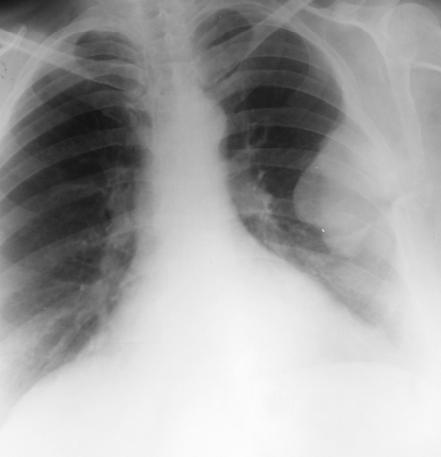

Rx toracică, incidență P-A

DESCRIERE:

DX: emfizem pulmonar

DD: